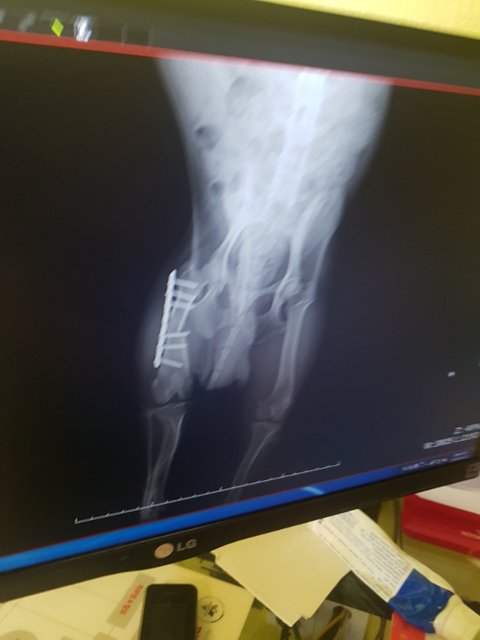

오늘 노아는 다리깁스도 풀고 실밥도 풀었습니다

다리가골이 잘 차고있고 경과가 좋아 이대로만 잘 아물면 된다고 합니다

그리고 오늘부터 사상충전처치약을 시작했습니다